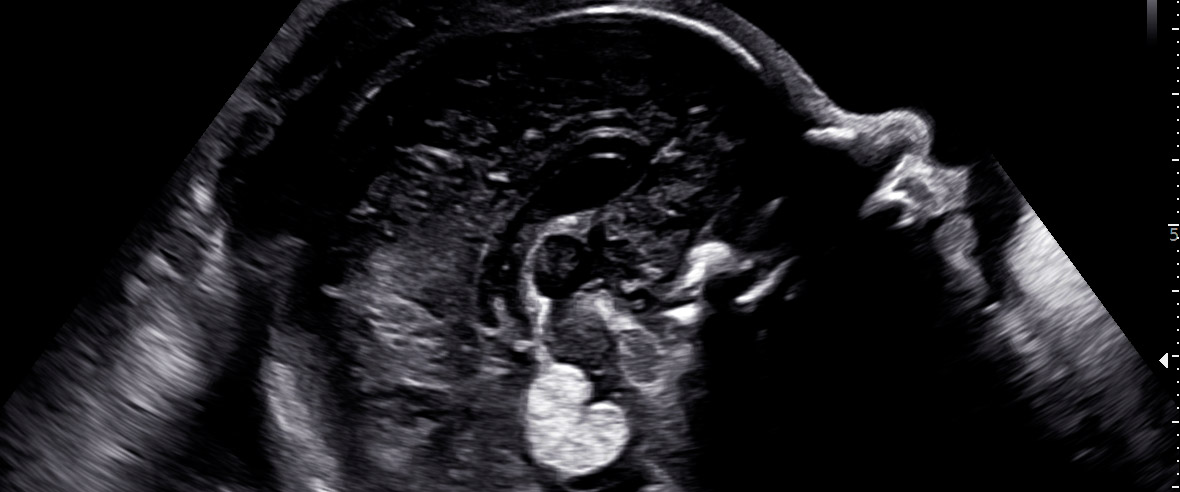

Medicina FetalEcocardiografia fetal: quando é indicada e o que a nova lei muda

Ecocardiografia fetal: saiba quando é indicada, o que avalia no coração do bebê e o que fazer se identificar uma alteração.